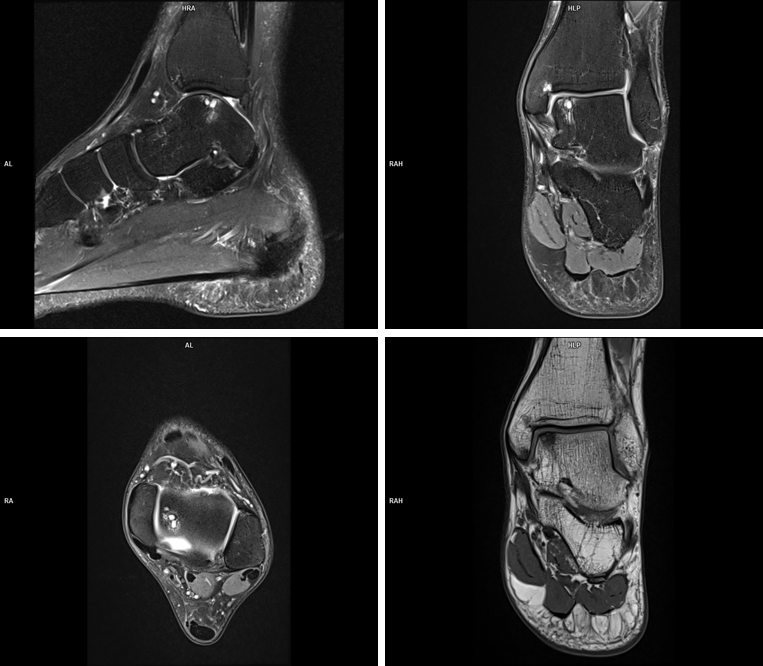

Figura 1: Colaj de imagini în ponderaţie proton density (PD) cu saturaţia grăsimii şi coronal T1 la nivelul articulaţiei tibio-talare

Deși părerea generală este că osul se vizualizează mai bine la computer-tomografie, acest caz demonstrează că prin examinare IRM se pune în evidență modificare de formă a osului talus superior si lateral – modificare ce nu se poate evidenția prin examinare CT, și acesta este un element important pentru diagnostic și planificare terapeutică. În plus, prin examinare IRM se poate vizualiza și cuantifica cartilajul articular.

Scopul publicării acestui caz este de a genera o discuție despre informațiile pe care le obținem la un pacient cu patologie ortopedica prin examinare CT și IRM. În folclorul medical se spune că medicul ortoped are nevoie de câteva radiografii și, eventual, o examinare CT pentru ca, împreună cu datele clinice, să poată pune un diagnostic și a indica un tratament. Știm deja că pentru o patologie de genunchi sau umăr se recomandă în general și examinare prin rezonanță magnetică deoarece articulațiile au multe grade de libertate și este util să vizualizam structurile tendinoase și musculo-ligamentare. Ce vedem în acest caz? Că examinarea prin rezonanță magnetică ne furnizează informații despre: cartilajul articular, structurile ligamentare și, mai mult, permite vizualizarea edemului osos care poate să fie sursă durerii pacientului.